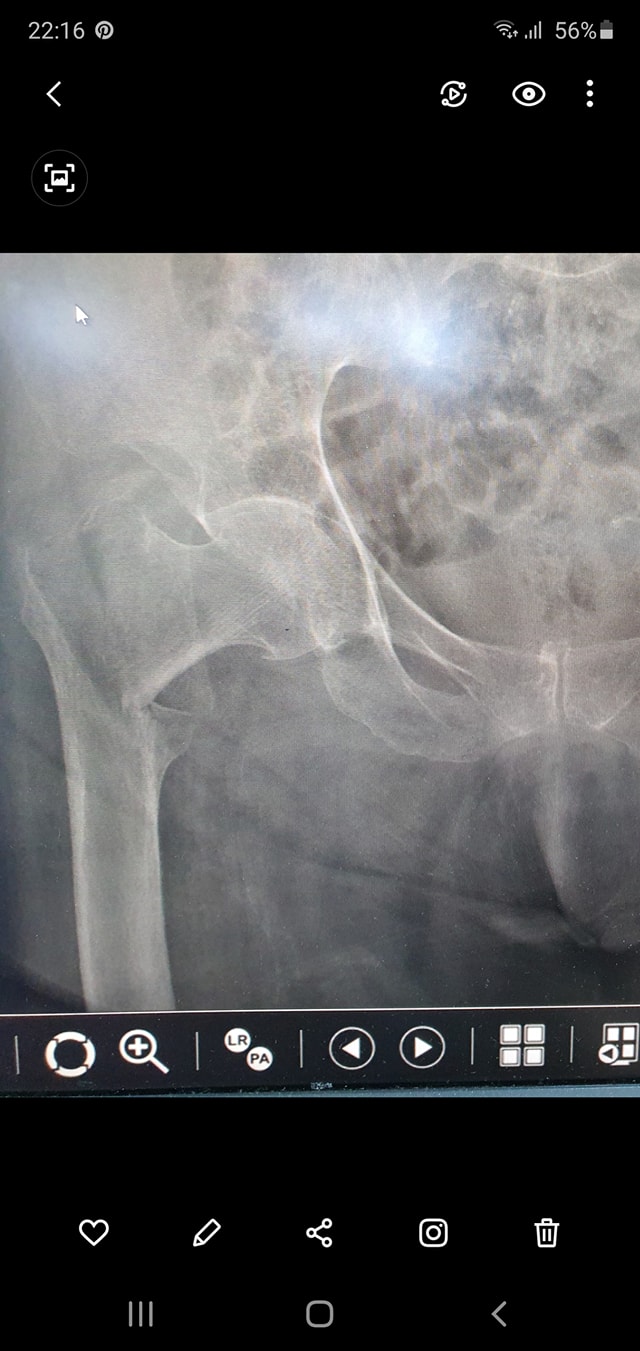

علاج خلع الورك الولادي بكافة ا